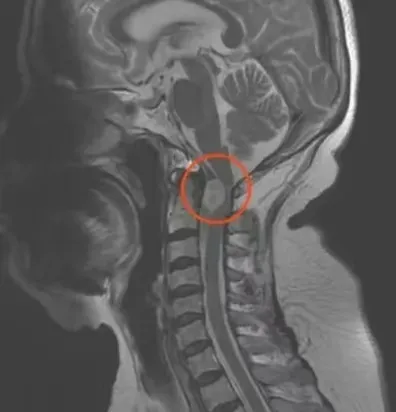

门诊医生详细问诊后,为其完善了磁共振检查,检查结果犹如一道晴天霹雳震懵了陈嬢嬢:磁共振影像上,她的后颈部赫然盘踞着一个占位性病变,犹如一颗潜伏的“夺命炸弹”,3.0 * 2 * 1.5 厘米的阴影触目惊心,沉甸甸压迫在脊髓之上,医生初步判断极有可能是神经源性肿瘤,威胁生命中枢。面对如此棘手的病例,科室高度重视。科主任蒋荣宽迅速组织全科人员展开深入讨论,最终拟定为患者实施颈1-2层面椎管内外占位性病变切除术。这是一项极具挑战性的四级手术,存在着诸多如脊髓损伤、血管损伤、神经损伤等高风险因素,每一个环节都如同在悬崖峭壁上行走,不容有丝毫闪失。